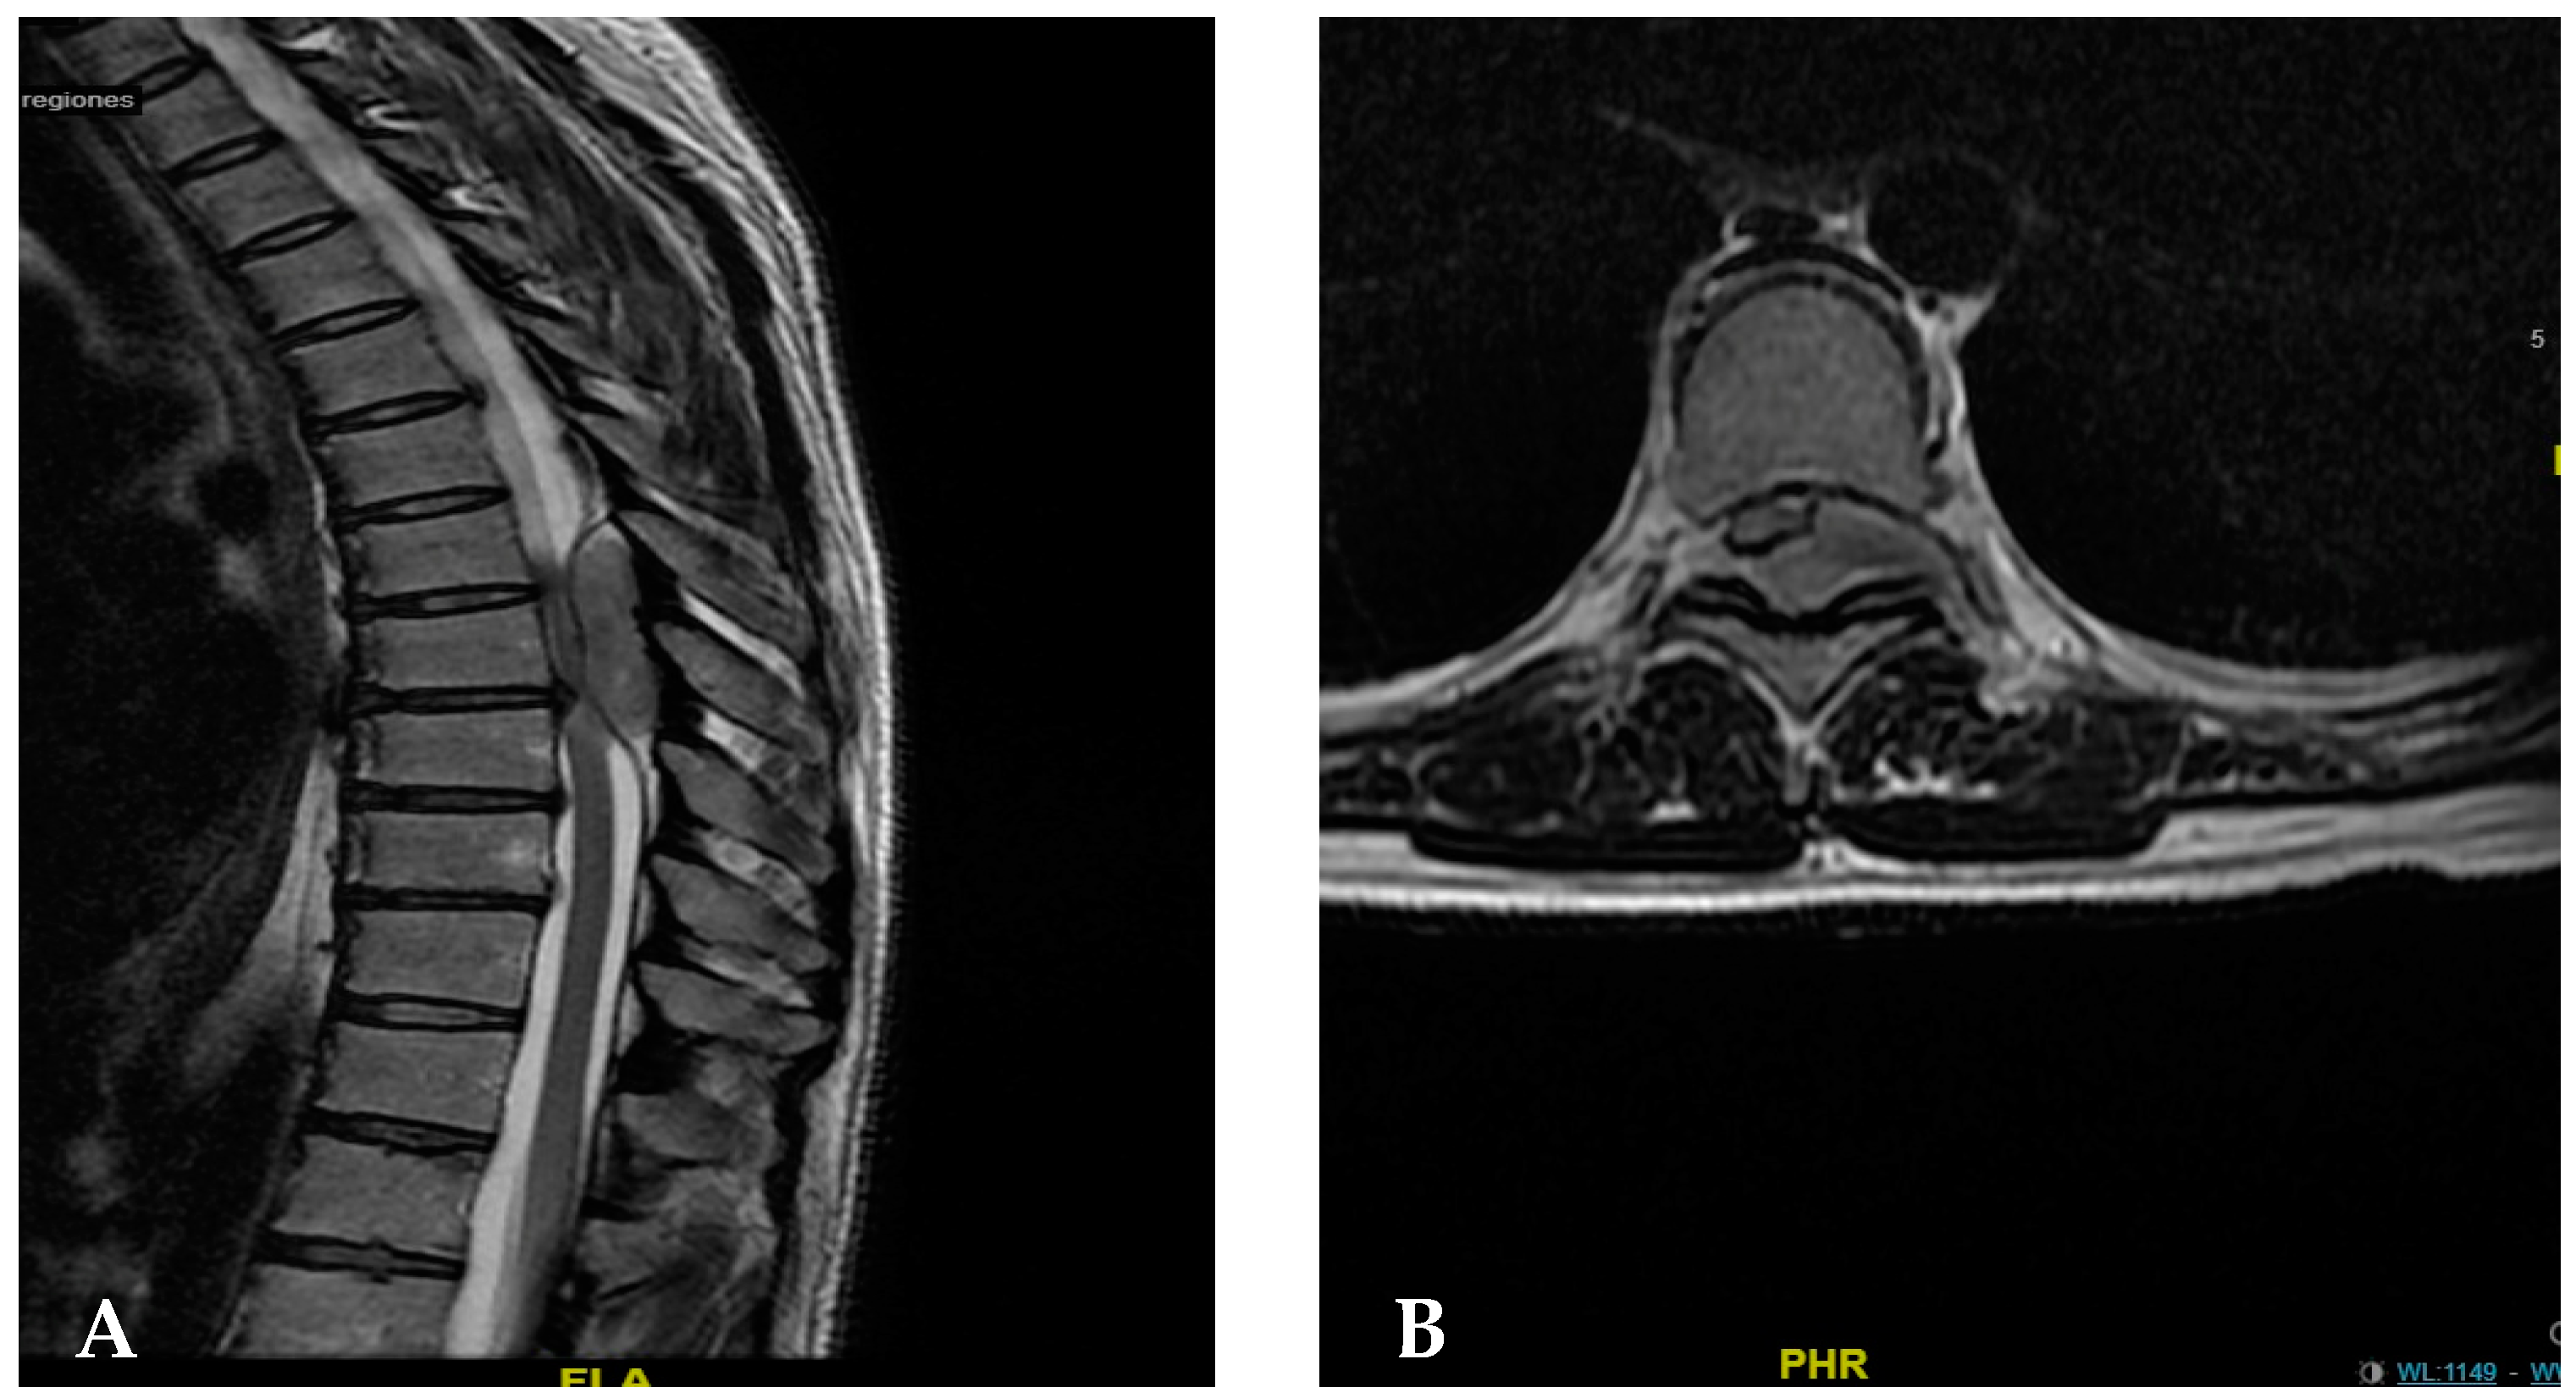

The physical examination and evaluation performed by the neurosurgery service included an imaging study, MRI (5 June 2023), and electrodiagnostic testing (somatosensory evoked potentials and electromyography). The assessments showed the following findings: 1. neuroconduction can be used to study pelvic limbs in normal ranges; 2. somatosensory evoked potential-based study of the pelvic limbs via tibial and peroneal nerves revealed no response on the left side and a slight delay in central conduction time via posterior cords; and 3. electromyography can be carried out without data regarding membrane instability. The magnetic resonance imaging of the thoracic and cervical region revealed an extradural hyperdense lesion at the T6–T8 level, compressing the medullary cord, and myelopathic changes in the spinal cord at the same level; likewise, sensory alteration was identified, with a loss of sensitivity from T10 (Figure 1).

Figure 1.

(A) Sagittal section magnetic resonance imaging performed to identify an epidural lesion causing the compression of the dural sac (blue arrow). (B) Magnetic resonance imaging in the axial section at the T7 level, showing an extradural image that displaces the medullary sac to the right side, and a lesion that invades part of the framen on the left side without apparent extraspinal invasion.